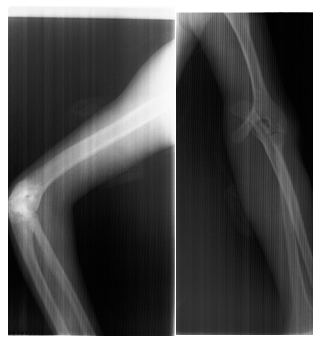

Radiographic limbs show bony ankylosis of the elbow joint, with associated hypoplasia of the ulna and proximal radius, leading to elbow flexion deformity on the left side (Figure 5). Chest x-rays show no apparent abnormalities: normal lung fields, cardiac silhouette, and bony structures (Figure 6) PA skull view show hypoplastic maxilla, prominent antigoinial notch and deviation of mandible to left side (Figure 7 &Table 1).

Figure 5 Radiograph of the left upper limb showing bony ankylosis of the elbow joint with hypoplasia of the ulna and proximal radius, resulting in an elbow flexion deformity.

In this case, the patient’s upper limb deformities, including shortening of the left upper limb and limited elbow extension, reflect the preaxial limb defects that are characteristic of Nager syndrome.21 The slight bowing of the lower limbs, although not a common feature, may represent an additional skeletal anomaly.9 The normal configuration of the patient’s fingers, with no signs of syndactyly or polydactyly, helps distinguish this case from other acrofacial dysostoses, such as Miller syndrome, which tends to present with postaxial limb defects.22